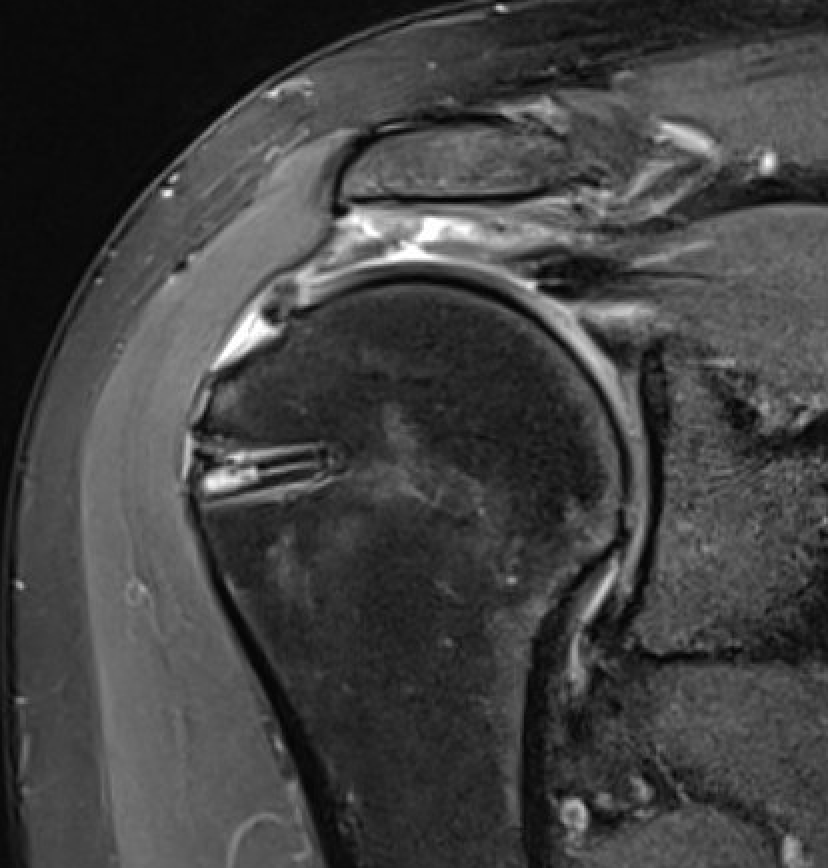

Double row anchors

- medial anchor row at articular margin and tie through medial cuff

- lateral anchor row at lateral footprint used to secure sutures

- increase surface area of cuff repaired to foot print

Trans-osseous equivalent / suture bridge

- cross sutures from medial row to lateral row

- increase contact between cuff and footprint